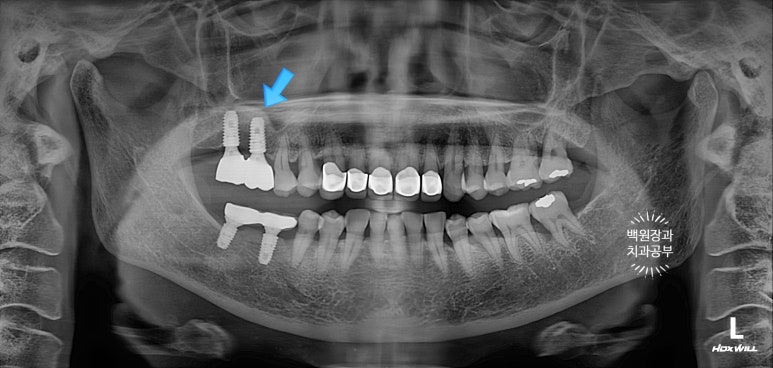

오른쪽 위 어금니 2개가 비어있어, 상악동 뼈이식술을 하면서 임플란트 2개를 심어드렸습니다.

이 것은 치주과 전문의인 제 작품입니다!! 두 명의 전문의가 상주하는 치과이지요 :)

임플란트 2차 수술을 마칠 당시, 상악동 뼈이식술을 했던 부위가 훨씬 확연하게 드러나는 것을 보실 수 있을거에요.

3년이 지나니 상악동 뼈이식술을 했던 곳은 이제 거의 내 뼈와 하나가 된 것처럼 예쁘게 성숙된 모습을 보여주고 있고, 앞니 지르코니아 크라운은 꼼꼼히 관리해주신 덕분에 충치 하나 없이 신경치료 하지 않았음에도 아주 잘~ 쓰고 있는 모습을 확인할 수 있었습니다!